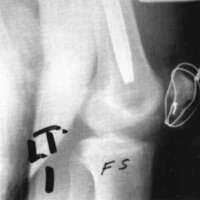

A twenty-nine year old male sustained a high caliber gunshot wound to the left knee (Fig. 4), traversing the lateral femoral condyle through the joint space and through the lateral tibial plateau. Open reduction internal fixation (ORIF) and ligamentous repairs were made. Postoperatively, the patient was placed in a standard cast brace due to the inability to provide adequate medial-lateral stability of the knee surgically (Fig. 5). The cast brace was attached to a continuous passive motion dynamic suspension system to restore and maintain motion (Fig. 6). At the time of the initial cast bracing, the patient had considerable soft tissue edema about the knee. The use of passive motion quickly reduced that swelling to the point where the cast brace provided little support. After one week, the cast brace was reapplied with the addition of a varus producing strap (Fig. 7) and the patient began ambulation training and was discharged. (If atrophy or swelling should continue, the varus producing strap can be easily adjusted to maintain force on the knee and another cast change would not be required).

Figure 7:

Figure 8: